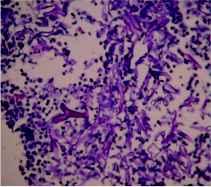

After 10 days of treatment, patient's diabetes was controlled but high grade fever and dyspnoea persisted. CT thorax was done which revealed necrotic soft tissue mediastinal mass measuring 5.1×4.7 cm in the right parahilar location (figure 1) closely encasing the bronchus intermedius and right inferior pulmonary vein. Few necrotic nodes abutting the primary mass lesion were also noted. Fiberoptic bronchoscopy revealed obstruction of right main bronchus with soft tissue with mucosal hyperemia. The material aspirated through trans-bronchial needle aspiration displayed non-septate fungal hyphae suggestive of zygomycosis on smear examination (figure 2).

Figure 2: The hematoxilin-eosin stain of the aspirate reveals broad, irregular, nonseptate, right-angled, branching hyphae of zygomyces (see arrow) against an eosinophilic and inflammatory background in the transbronchial aspirate smear.